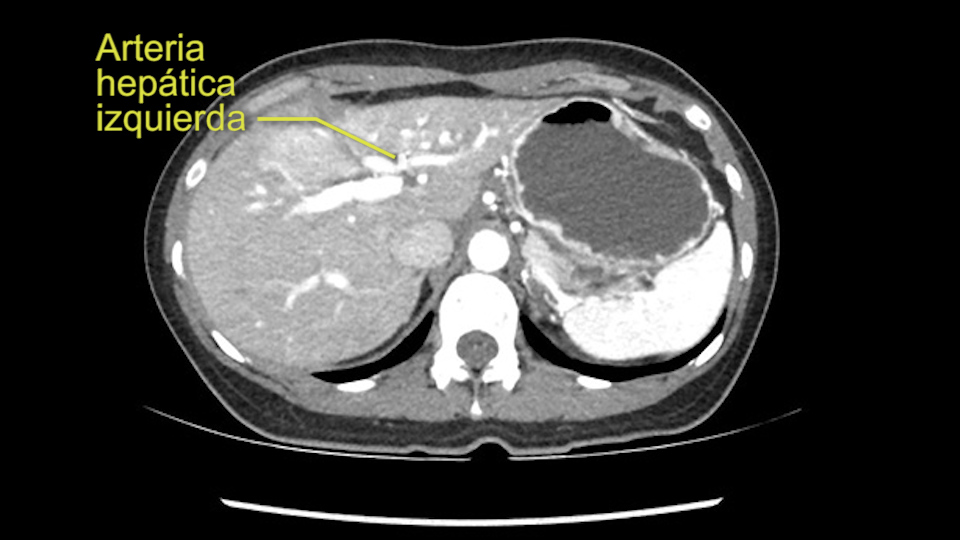

En cuanto a la técnica quirúrgica lo primero que hago es mirar al escáner a la fase arterial que tenemos aquí y claramente ese ve como los hepatocarcinomas son tumores muy vascularizados se pude como las ramas de la arteria hepática izquierda hay muchas ramas nutriendo a este tumor, parece que son bastantes grandes. Parece claro que todas las ramas yendo al hígado derecho están libres de tumor y yo no creo que haya ninguna invasión vascular en este caso. Y como se puede ver hay una gran masa que insisto parce que cuelga del segmento 3.

Muchas ramas de la arteria hepática izquierda al tumor